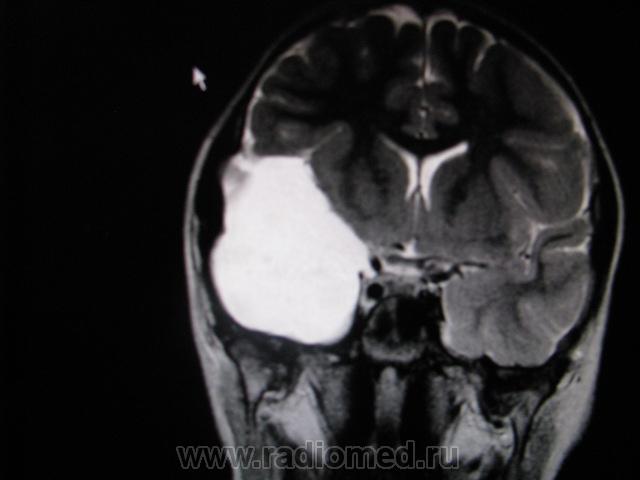

Крупная арахноидальная киста правой височной области.

да, до этого мальчик жалоб не предъявлял. наверное киста увеличилась, масс-эффект на прилежащие струкутры усилился , появилась клиника.

Да, это врожденная арахноидальная киста.